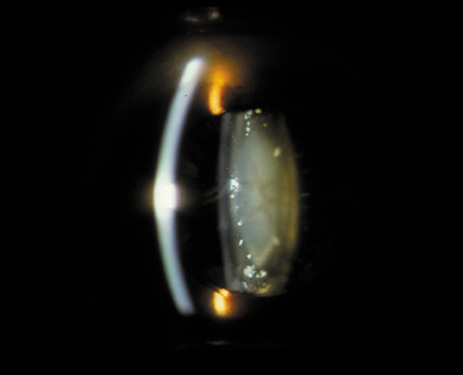

Nuclear cataracts tend to progress slowly. The refractive index of the lens changes as the nucleus progressively hardens, which usually results in increasing myopia.20,21 In some patients this is accompanied by optical distortion, especially of distant images, while near vision remains unaffected. A nuclear cataract is best seen with the narrow-beam direct illumination employed by the slit-lamp, which reveals the color and generalized haze or opalescence of the nucleus. In the early stages, the two halves (cotyledons) of the embryonic nucleus remain visible (Fig. 3). Later the entire nucleus appears as a homogeneous mass in contrast to the cortex (Fig. 4). Retroillumination may show the “oil droplet” effect (Fig. 5). Sometimes one may notice crystals in the lens nucleus (known as a Christmas tree cataract; Fig. 6A and B).

Fig. 6. Slit-lamp appearance of a Christmas tree cataract, showing crystals in the nucleus.